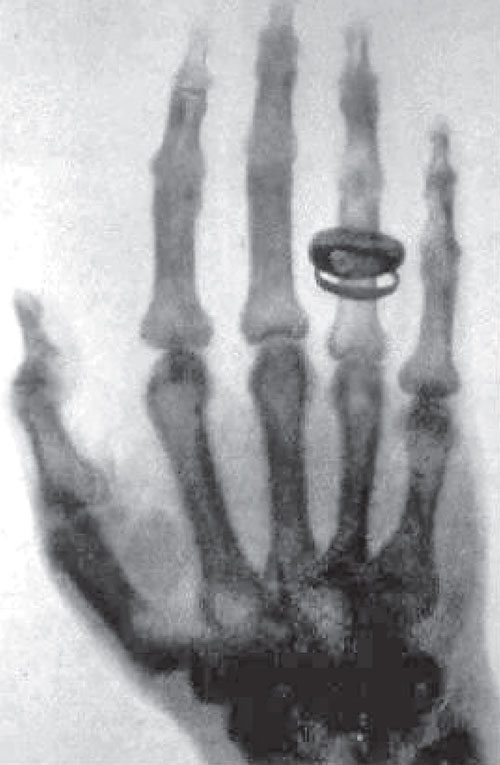

1895 年,德国物理学家伦琴(图 8–23)在研究阴极射线时发现了 X 射线,他给他妻子的手拍了一张 X 光照片,如图 8–24 所示,故 X 射线又称为伦琴射线。X 射线的波长约为 10−11 ~ 10−8 m,具有很强的穿透能力。

图 8–24 伦琴首次拍到的他夫人手的 X 光照片